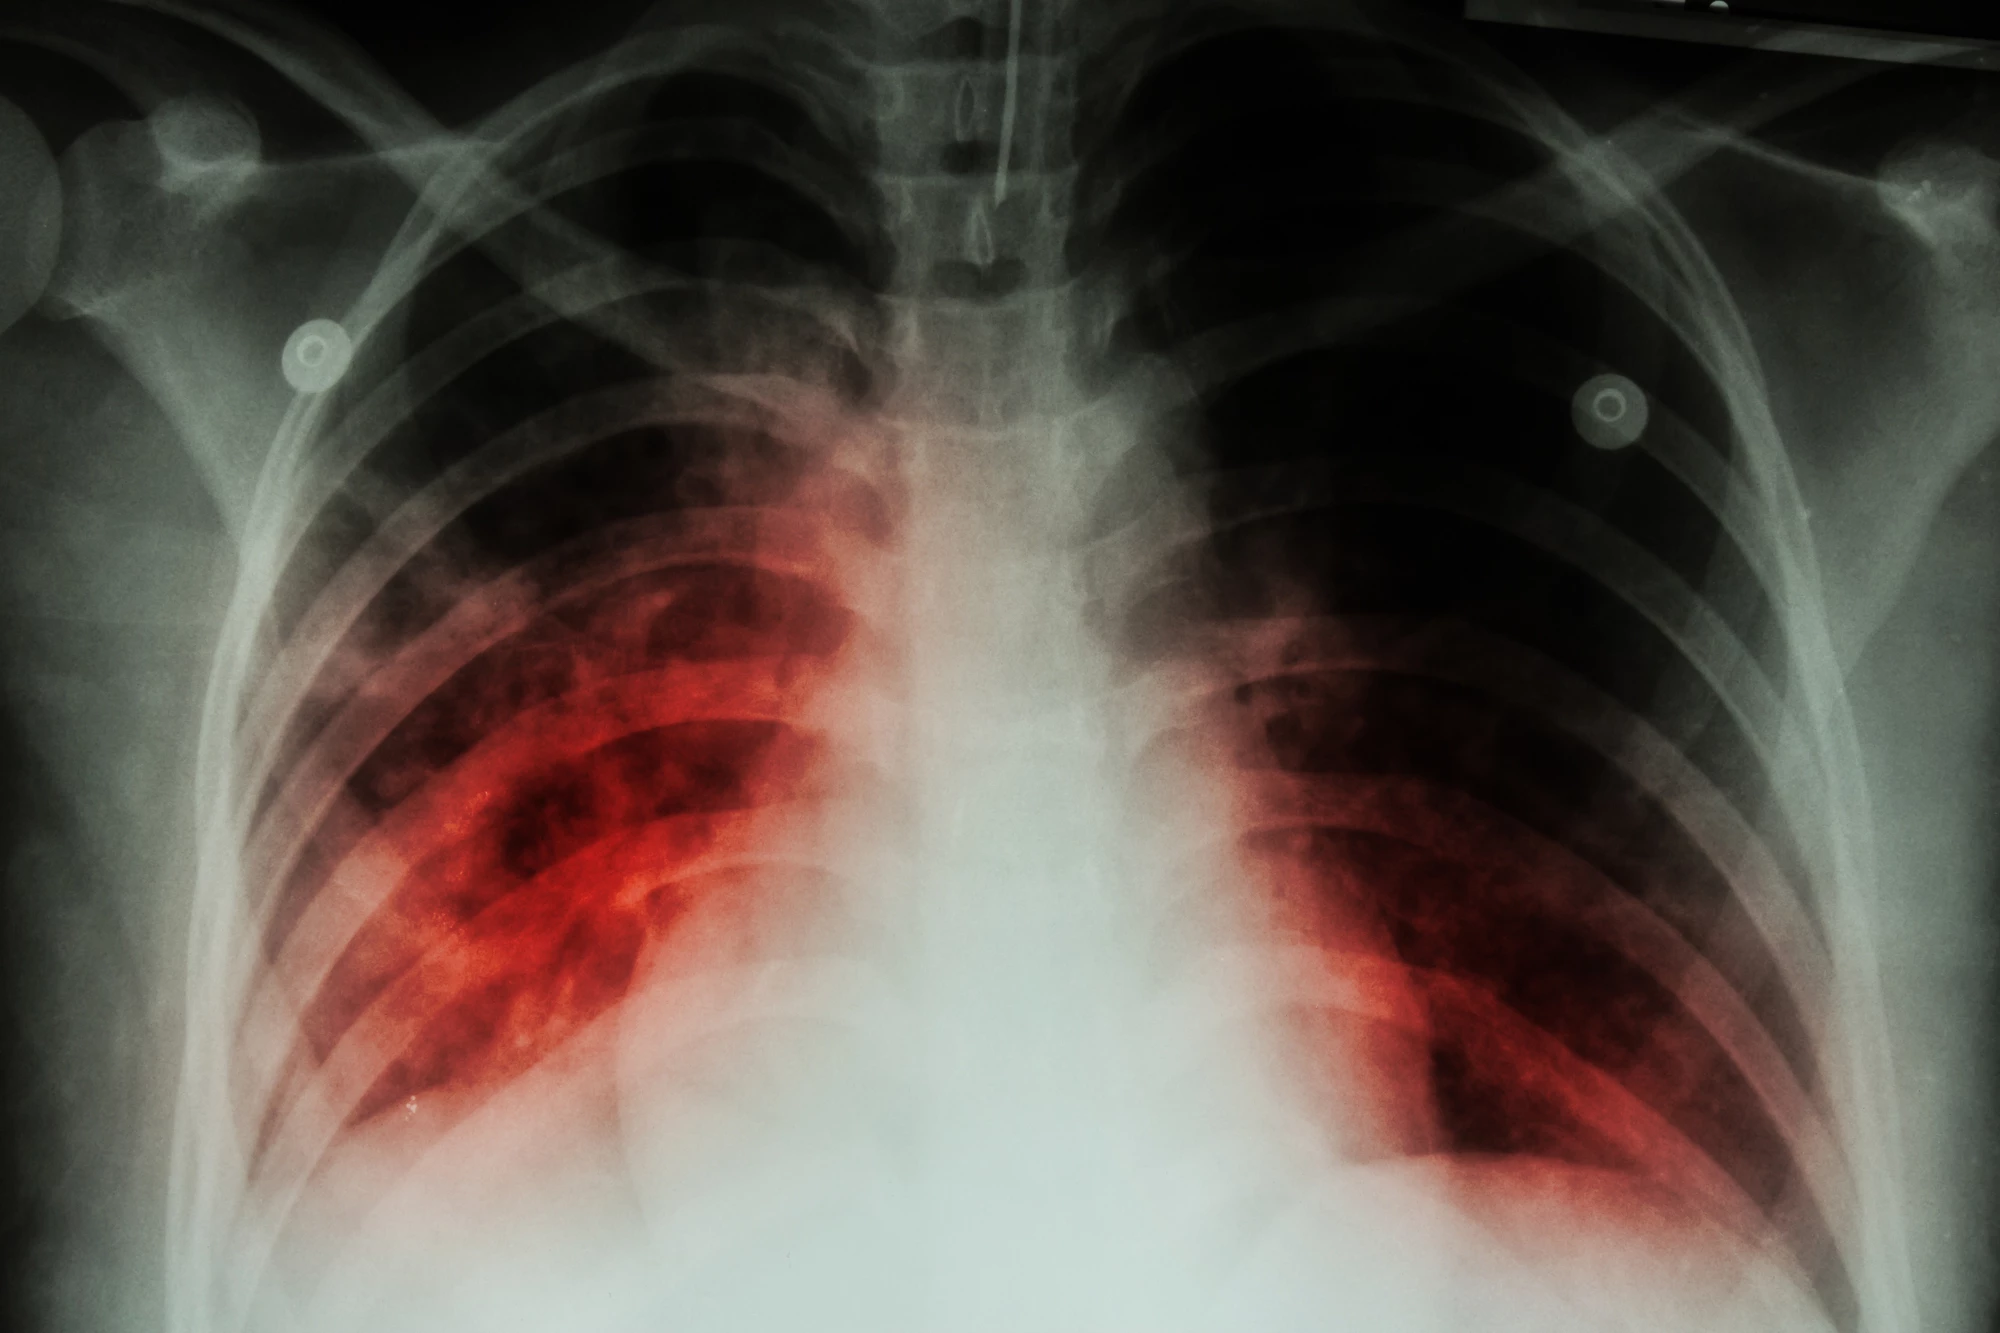

It's hoped a new vaccine will be the first new TB vaccine to be successfully developed in 100 years